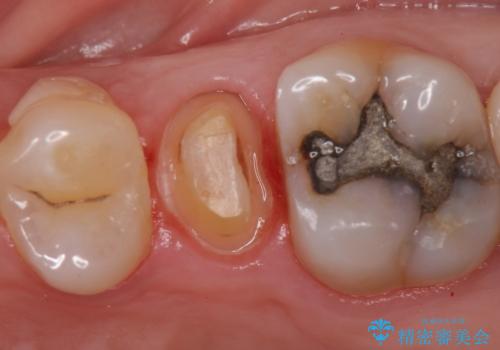

- 左上5番目の歯がしみるといらっしゃった方の症例です。

頬側の樹脂及び銀歯を除去後、オールセラミッククラウンにて補綴を行いました。